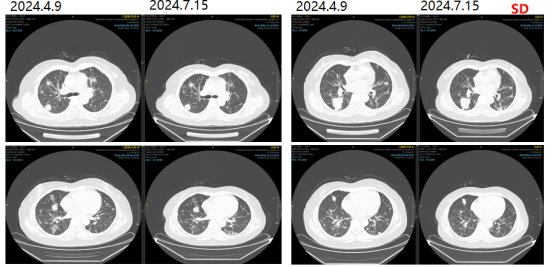

更换治疗方案为西妥昔单抗+XELIRI方案。2023-12-05、2024-01-03分别予西妥昔单抗+XELIRI方案 q3w。

图7影像学复查结果

2024-01-26、2024-02-20、2024-03-16继续予靶向+XELIRI方案化疗4疗程。

出现粒细胞缺乏,化疗后48小时皮下注射PEG-rh-GCSF。

2024-04-09评估疗效疾病稳定(SD)。

图8影像学复查结果